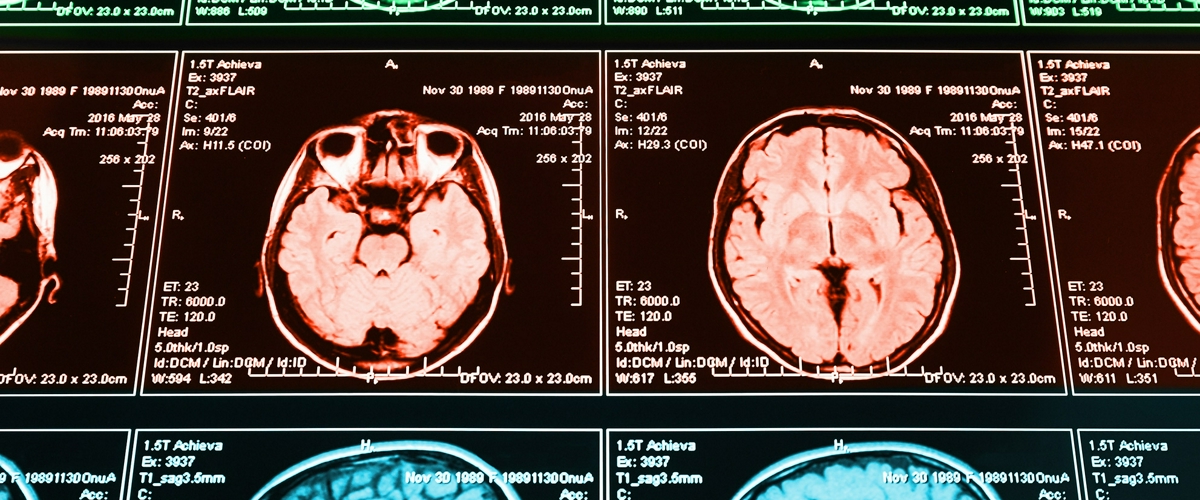

Команда собрала масштабный пазл из данных 1003 абсолютно здоровых людей. Они совместили результаты функционального и диффузионного МРТ с подробнейшей информацией о поведении, возрасте, эмоциональном состоянии и даже уровне IQ. Задача — найти не просто активную зону, а целый паттерн, алгоритм работы мозга, который предрасполагает к вспышкам ярости.